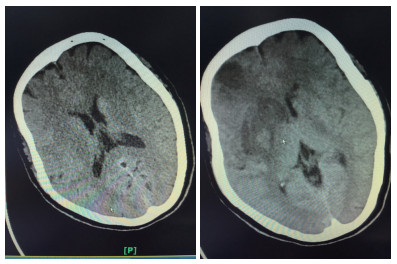

患者女性,55岁,住院号:526777。主诉:左侧肢体乏力1 h余。现病史:缘于入院前1 h余始无明显诱因出现左侧肢体乏力,持物、行走不能,伴有构音含糊,无吞咽困难、饮水呛咳,无意识障碍,无抽搐、二便失禁,无头晕头痛呕吐,无畏冷发热,无咳嗽咳痰,无心悸气喘,无腹痛腹泻,无双下肢水肿。在外未诊治,急诊行头颅CT后送入本科。既往史:无。个人史:无烟酒嗜好。体格检查, 查体:体温: 36.5℃, 脉搏: 72次/min, 呼吸: 20次/min, 血压: 126/76 mmHg。双肺呼吸音清,未闻及干湿性啰音;心率72次/min,律齐,各瓣膜区未闻及杂音;周围血管征阴性;专科查体:神志清楚,构音含糊,对答切题,双眼向右侧凝视,左侧鼻唇沟浅,口角歪向右侧,伸舌偏左,左侧肢体肌力1级,右侧肢体肌力5级,肌张力正常,深、浅感觉正常,膝反射、跟腱反射等腱反射对称活跃,克匿格征、布鲁金斯基征阴性,左侧巴彬斯基征阳性,右侧病理征未引出,共济运动及闭目难立征欠合作。NIHSS评分14分。辅助检查:头颅CT示双侧基底节区腔隙性脑梗死;入院诊断:①脑梗死②糖尿病?治疗;患者处于溶栓时间窗,入院后完善相关检查无明显溶栓禁忌证,经家属同意,予阿替普酶溶栓(患者体质量55 kg,予阿替普酶50 mg溶栓,其中5 mg静推,余剂量予1 h泵入),并予“吡拉西坦8 g静滴,1次/d,依达拉奉30 mg静滴,2次/d”等治疗,第2天患者左侧肢体乏力、构音含糊较前改善,查体:构音稍含糊,双眼无凝视,左上肢肌力1+级,左下肢肌力3级,溶栓后第1天复查颅脑CT平扫:右侧基底节区及额颞叶大面积脑梗死,并右侧基底节区出血性脑梗死可能性大(阅片考虑可疑高密度灶非出血灶,考虑正常脑组织),予加用波立维75 mg,1次/d、立普妥20 mg每晚睡前1次、尤瑞克林0.15 PNA静滴,1次/d。溶栓后第2天颅脑MR平扫(1.5T):①双侧基底节区、双额叶多发梗死灶、腔隙灶。②脑干腔隙灶?③部分空泡蝶鞍。患者住院共11 d,出院时患者左侧肢体乏力、构音含糊较前改善,查体:构音稍含糊,双眼球活动正常,左侧鼻唇沟略浅,口角略歪向右侧,伸舌略偏左,左上肢肌力2+级,左下肢肌力4+级,NIHSS评分5分。